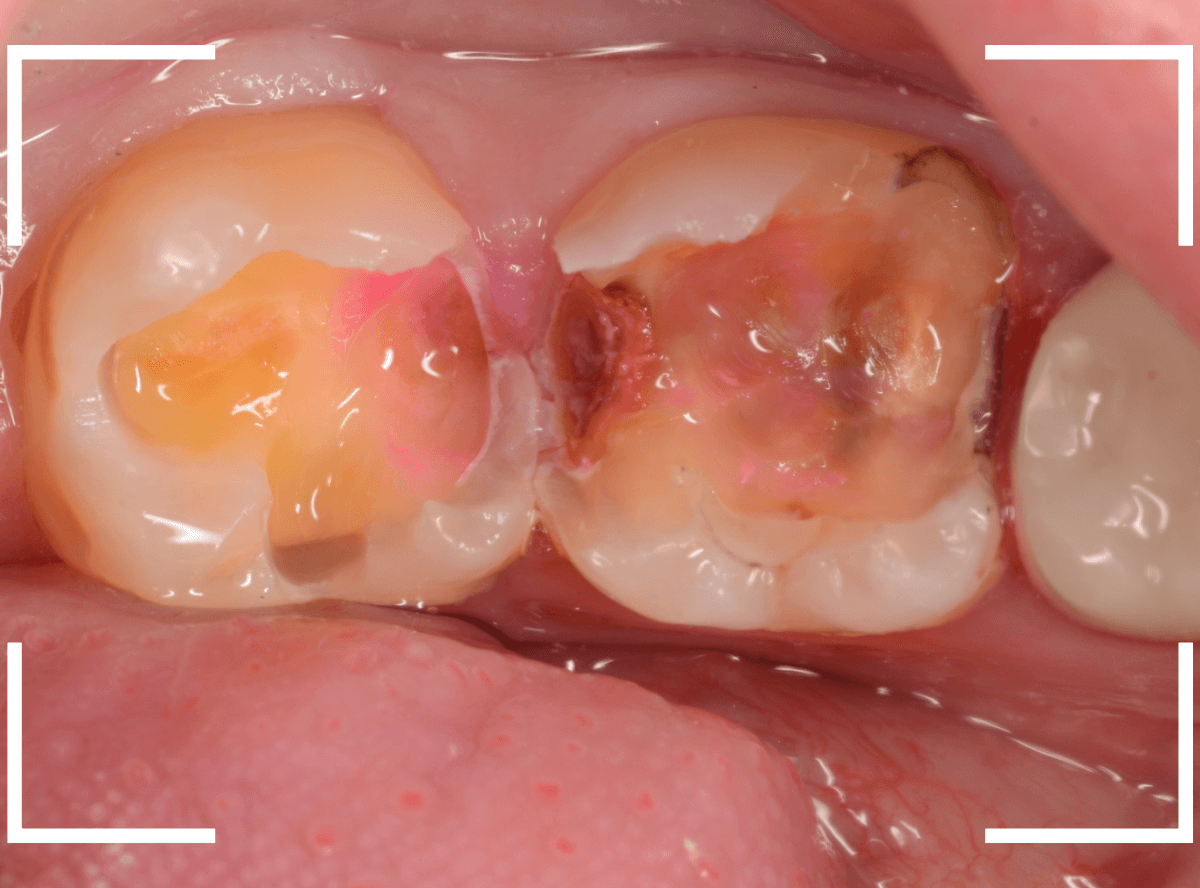

8~9割ほどの虫歯が除去できたかというところですが、

赤く染色されている部分などがまだ虫歯が残っている部分です。

いよいよ神経に近い虫歯まで到達しましたので、手で操作するため、より繊細に虫歯を除去できるエキスカベーターを使用します。

エキスカベーターを使ってほぼ全ての虫歯を除去したところです。

幸い、神経寸前で虫歯はとどまっていましたが、お薬を詰めて、しばらく経過観察します。